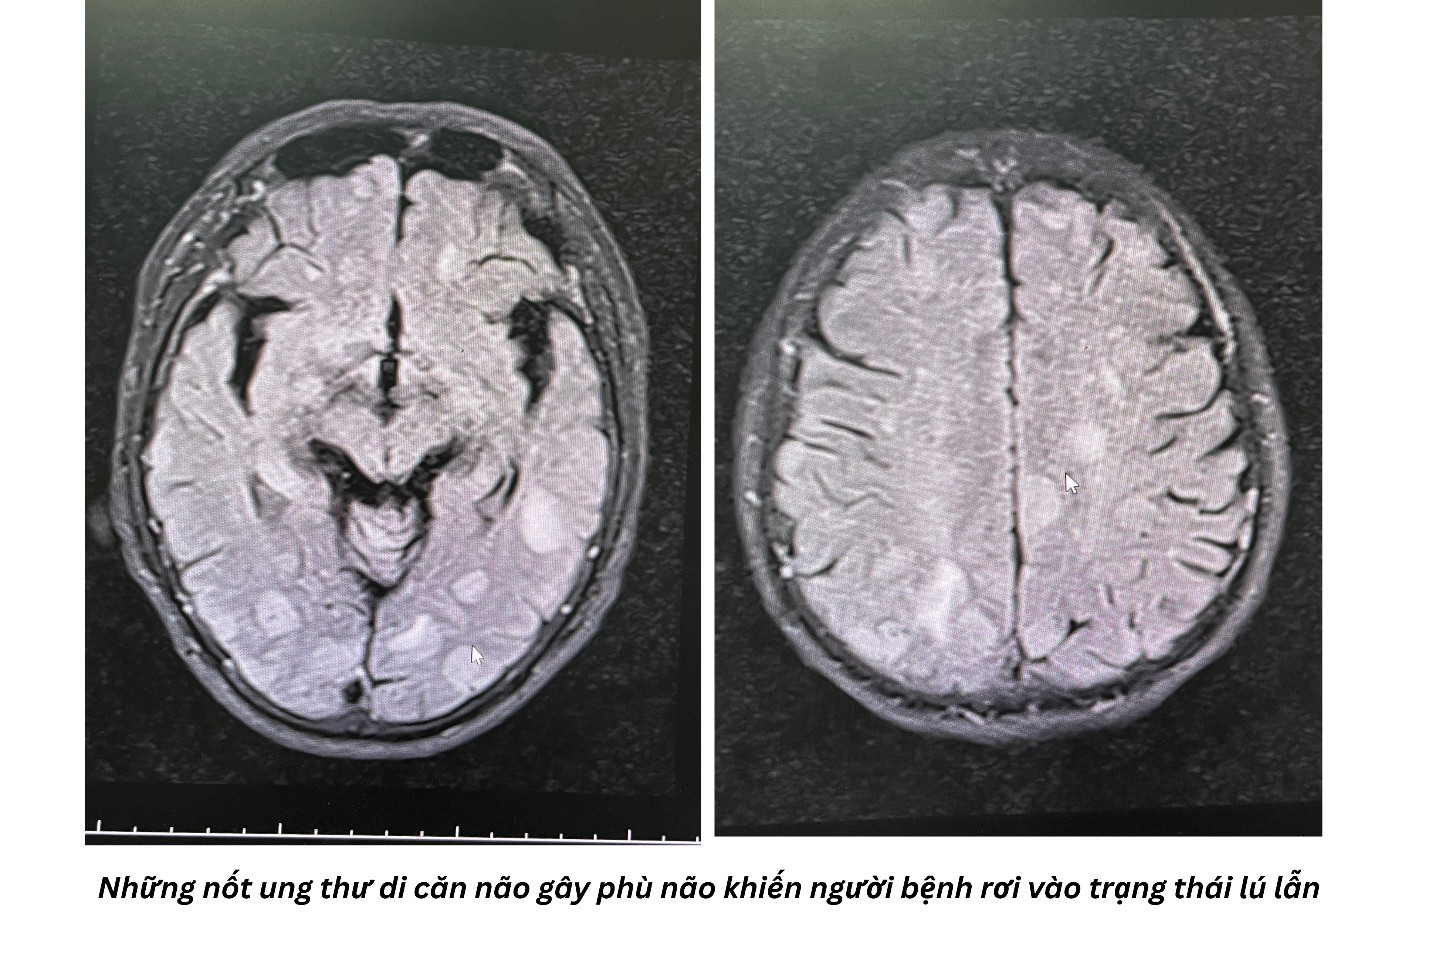

Tình trạng phù não nghiêm trọng khiến bác R. rơi vào trạng thái lú lẫn, mất định hướng, không còn nhận ra người thân. Mọi sinh hoạt cá nhân từ ăn uống đến vệ sinh đều phải phụ thuộc hoàn toàn vào gia đình do bệnh nhân đã mất khả năng đi lại.

ThS. BS. Nguyễn Ngọc Hoàng, Trưởng khoa Xạ trị, PGĐ Trung tâm Ung bướu cho biết: “Trường hợp của bệnh nhân R. là một thách thức lớn, bởi khối u đã di căn gây phù não diện rộng trên nền bệnh lý tiểu đường và rối loạn điện giải. Nếu không can thiệp kịp thời bằng xạ trị, bệnh nhân có nguy cơ tử vong cao hoặc sống thực vật. Chúng tôi đã quyết định ứng dụng kỹ thuật xạ trị toàn não nhằm tiêu diệt các tế bào di căn, giảm áp lực nội sọ và kiểm soát tình trạng phù não”.

Kết quả đã vượt xa sự mong đợi của gia đình và đội ngũ y bác sĩ. Chỉ sau hơn 2 tuần điều trị với 10 mũi, tình trạng phù não của bác R. giảm rõ rệt. Từ một người không còn ý thức, bệnh nhân đã tỉnh táo, nhận biết được mọi người xung quanh và đặc biệt là đã có thể tự đứng dậy đi lại trong sự ngỡ ngàng của người thân. Điều này cũng tạo điều kiện thuận lợi cho các bước điều trị tiếp theo.